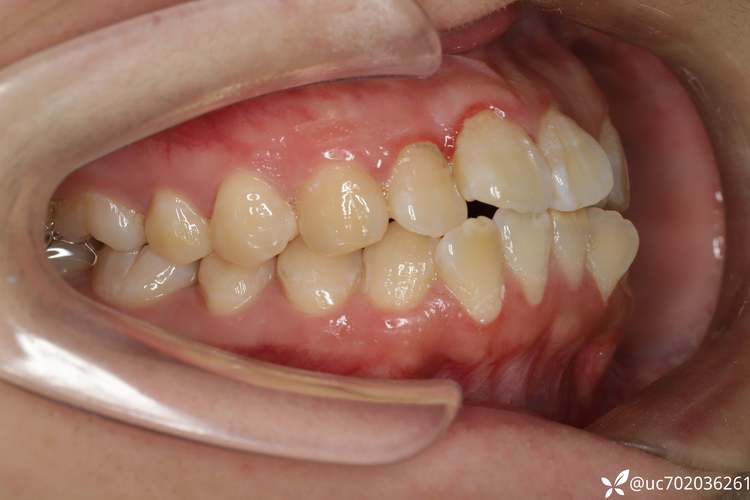

拔牙在正畸中的核心目的是“创造空间”,无论是青少年还是成年人,当牙齿存在严重拥挤、前突(“龅牙”)、咬合紊乱等问题时,单纯依靠移动现有牙齿可能无法达到理想效果,此时拔除部分牙齿(通常为前磨牙或智齿)能为其他牙齿的排齐和咬合调整提供必要空间,对于牙列严重拥挤的情况,拔牙后可以将内收的牙齿排列到牙弓正常位置,不仅改善美观,还能降低清洁难度,减少未来龋齿和牙周病风险,对于中老年人而言,拔牙正畸的考量更为复杂,因为他们的牙齿往往伴随磨耗、牙周退缩、牙槽骨吸收等问题,正畸前需全面评估牙周健康状况、牙根长度及全身疾病(如糖尿病、高血压)控制情况,确保治疗安全。

中老年人正畸的“老了”因素,主要体现在牙周健康和牙齿长期稳定性上,年轻时牙槽骨密度高、牙周组织修复能力强,正畸后牙齿移动和恢复相对容易;而中老年人群牙槽骨可能出现生理性吸收,牙龈也可能存在萎缩,若正畸前存在未经治疗的牙周炎,强行移动牙齿可能导致牙槽骨进一步破坏,甚至牙齿松动脱落,中老年正畸前必须进行系统的牙周治疗,控制炎症,待牙周状况稳定后再开始正畸,拔牙选择上,医生会更倾向于优先拔除牙周条件差、无保留价值或影响咬合的牙齿(如严重龋坏、残根),而非单纯为了排齐而拔除健康的牙齿,中老年正畸的疗程可能更长,牙齿移动速度较慢,需要医患双方更有耐心。